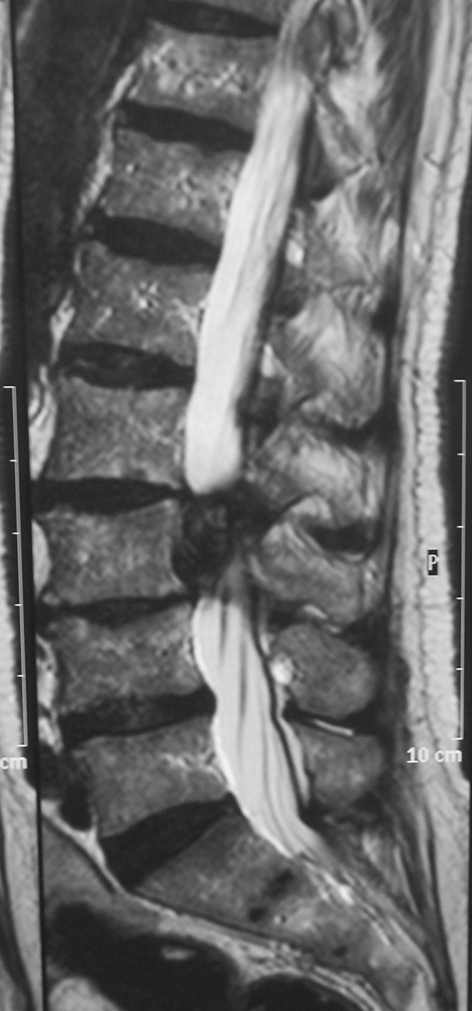

A lumbo-sacral MRI showed a well encapsulated paramedian multilobar mass under the L3 body, along the left L3 root (Figs. 3, 4).

Fig. 3.

Case 2, axial L3 preoperative T2 MRI sequence